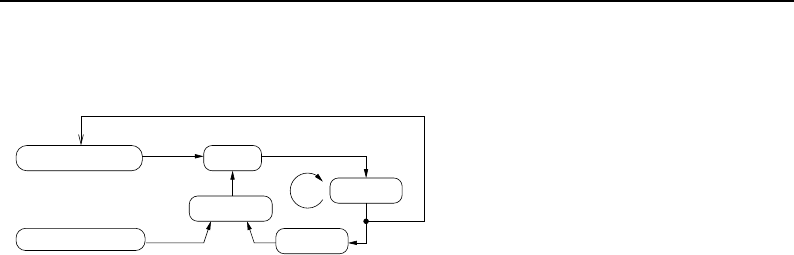

- Segmentation

- Statistics